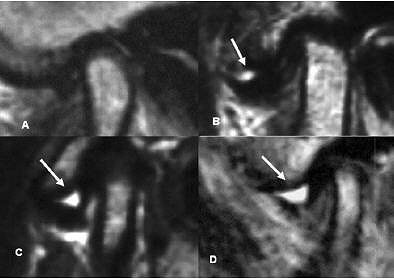

| Classification of "with" and "without" joint effusion. Arrows indicate joint effusion. (A) no effusion, (B) minimal effusion, (C) moderate effusion, (D) marked effusion. Panel A was without joint effusion. Panels B-D are examples with joint effusion. K Matsumoto, K Honda, K Sawada, T Tomita, M Araki, and Y Kakehashi. "The thickness of the roof of the glenoid fossa in the temporomandibular joint: relationship to the MRI findings," Dentomaxillofac Radiol 2006 35: 357-364. |

More specifically, there were 70 normal joints, 53 joints with ADWR, and 51 joints with ADWOR. The average minimum thickness of the RDF was 0.85 mm in normal joints, 0.90 mm in ADWR joints, and 0.93 mm in ADWOR joints.

Based on additional analysis, there were 21 joints with osteoarthritis (OA), 153 without OA, 61 with joint effusion, and 113 without joint effusion. The RGF thickness in the OA group was 0.99 mm versus 0.87 mm in the group without OA. RGF thickness in 33 joints with disk deformation was 0.87 mm compared to 0.89 in 141 joints without disk deformation.

However, there was a significant RGF thickness between the groups with joint effusion (0.97 mm) and those without joint effusion (0.84 mm), the authors stated, indicating that RGF thickness is influenced by joint effusion.